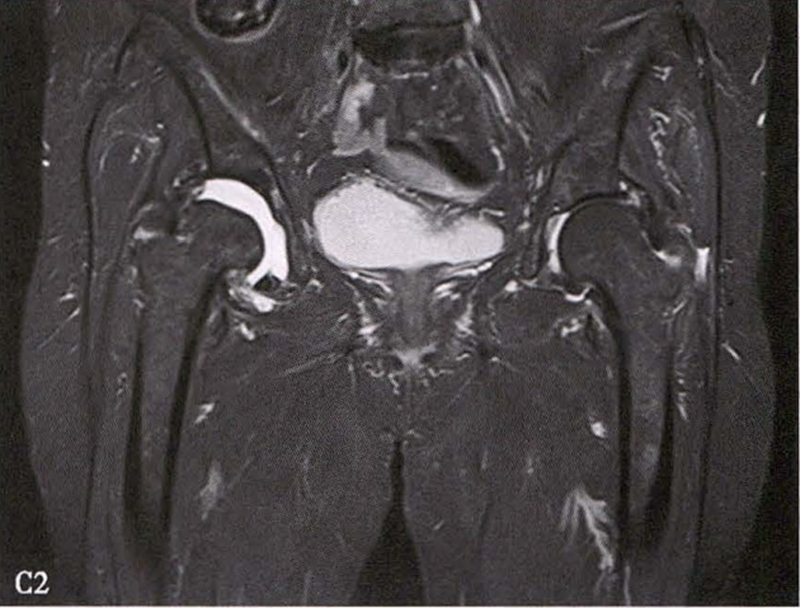

(2)MRI检查 MRI检查是早期诊断股骨头坏死最具特异性、灵敏度的检查方法。当怀疑有股骨头坏死,而X线片无明显异常时,应行MRI检查。诊断时可根据髋关节X线、MRI显示的坏死面积和塌陷程度进行ARCO分期。

冠状面及横断面MRI图像

MRI示双侧股骨头坏死,冠状面显示右侧股骨头坏死(图A、C),横断面显示双侧股骨头坏死(图B、D);T1加权像(图A、B)显示硬化带为低信号,T2加权像(图C、D)显示右侧骨坏死硬化带外围高信号的骨髓水肿,左侧无骨髓水肿。

C.女性,89岁,右侧股骨头坏死Ⅳ期。X线片示右侧股骨头压缩变扁,右侧髂臼密度增高,关节内侧间隙狭窄、不均匀(C1)。MRI示右股骨头压缩变扁,右髋关节腔比较多积液(C2)。